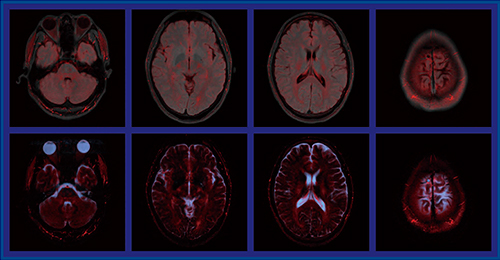

図5はボランティアによるアキシャルのカラーマップで,同じデータを基に間質液(上段),脳脊髄液(下段)に注目して作成している。いくつか興味深いポイントがあり,例えば,脳脊髄液の中にT2の短いところもあり,均一ではないことが見て取れる。また,コロナル(図6)やサジタルでは,錐体路に沿うように大きな流れや,頭頂付近の硬膜内にリンパ系と思われるT2の短い部分が見られる。リンパ系と脳内の交通は最近のホットトピックであり,今後臨床で検討し,脳の水動態の解明に取り組んでいきたい。

図5 ボランティアによる検討結果:アキシャル

上段:間質液,下段:脳脊髄液